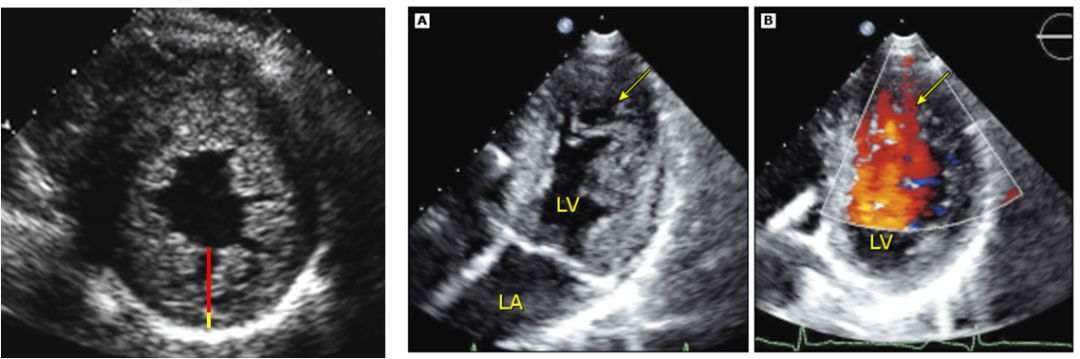

超声心动图可用于诊断LVNC,并可在随访中作为辅助检查。各中心已提出了下列关于LVNC的超声心动图标准:

左心室壁增厚,包括2层:一层较薄的致密化心外膜层和一层显著增厚的非致密化心内膜层,内层有数目众多的突出小梁形成和深陷的小梁间隐窝,并且胸骨旁短轴切面上收缩末期非致密化心肌与致密化心肌(non-compacted to compacted, NC:C)的最大比值大于2:1

彩色多普勒成像可见深陷的小梁间隐窝内血流的证据

左心室下壁和侧壁的心尖段或中段有明显的小梁网状组织

X与Y的比值小于等于0.5;X代表的是心外膜表面与小梁隐窝底部间的距离,Y代表的心外膜表面与小梁顶端间的距离。此诊准应用于剑突下或心尖四腔切面上舒张末期左心室心尖部的小梁。

在单个成像平面中,从心尖水平到乳头肌水平可以见到3条以上从左心室壁突出的肌小梁。

彩色多普勒成像可见小梁间隙来自心室腔的血液灌注